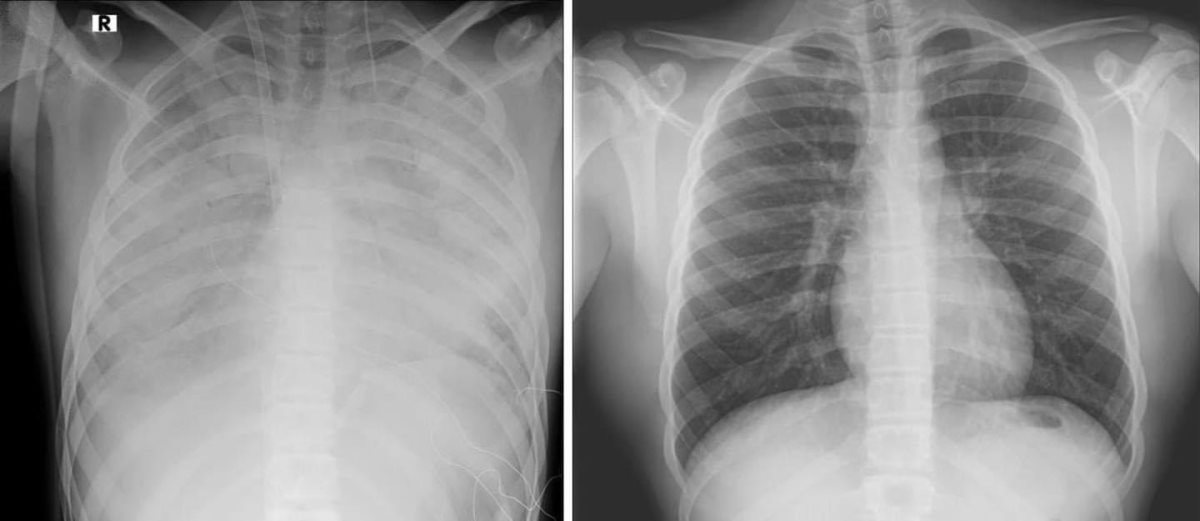

נער בן 16 אושפז במרכז שניידר במצב קשה עם קריסה של הריאות לאחר שימוש בסיגריות אלקטרוניות. הנער הובהל ליחידה לטיפול נמרץ לב, שם הוא מאושפז בהכרה ומחובר למערכת האקמו, המחליפה את פעילות הלב והריאות - כך מפרסמים הבוקר כתבי אתר ויינט, רענן בן צור וגד ליאור.

הנער הועבר למרכז שניידר מבית החולים קפלן, לאחר שריאותיו קרסו. מבירור רפואי מקיף שערכו בבית החולים קפלן עלה כי מצבו הידרדר כתוצאה מעישון של סיגריות אלקטרוניות.